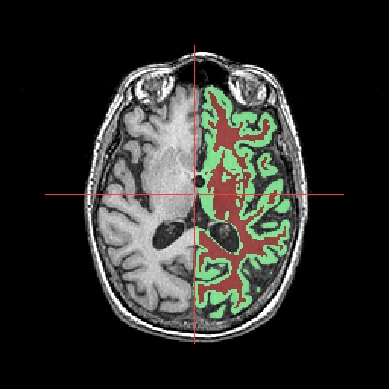

Objects fusion enables to create a new object from 2 or more other objects. Indeed, if you only put two volumes in the same window, you will see only one. To see the two volumes, you need to mix voxels from the two volumes in order to obtain a new volume. Note that fusionning more than 2 objects is only possible since 1.30 version. Besides, several new features have been added for fusion management. Several fusion combinations between objects are available,but for the moment, let’s see a fusion between two 3D volumes for example:

STEP 1: Load the images to merge. Here, we will fusion an anatomy and the brain mask obtained from BrainVISA anatomical pipeline.

Example of a linear fusion between two 3D volumes¶